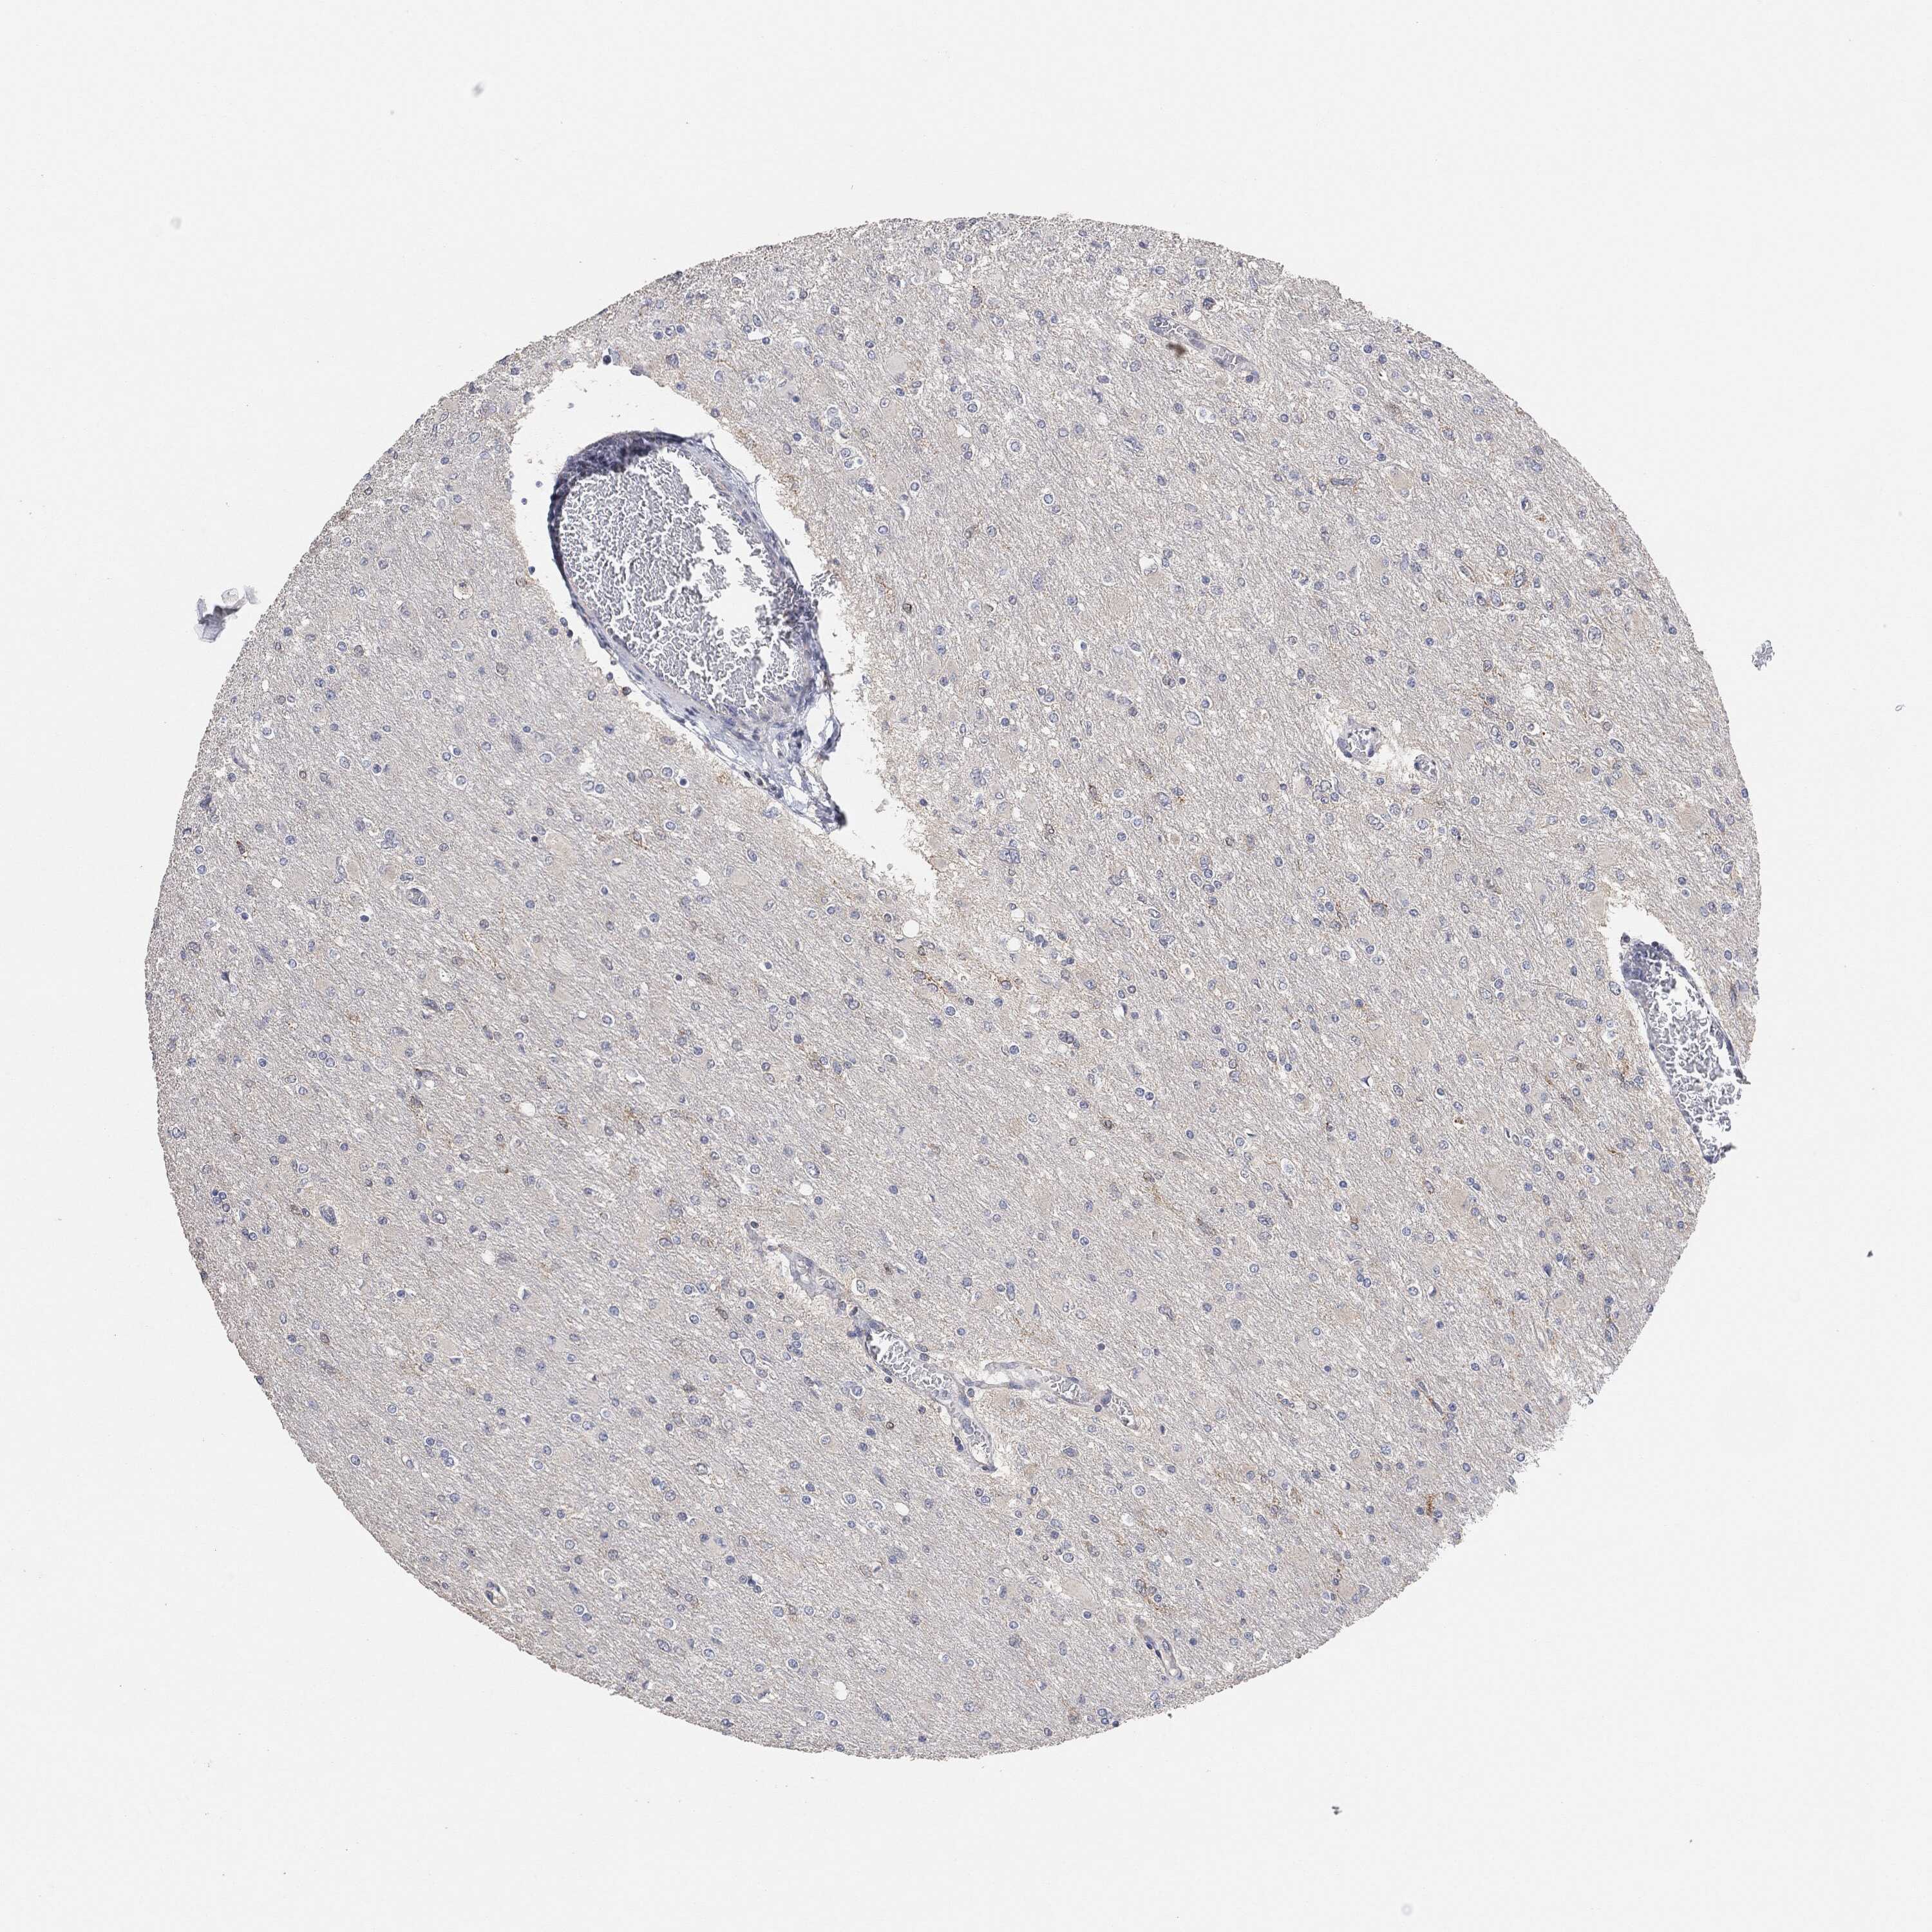

GLIOMA - Protein expressioni

A mouse-over function shows sample information and annotation data. Click on an image to view it in a full screen mode. Samples can be filtered based on level of antibody staining by selecting one or several of the following categories: high, medium, low and not detected. The assay and annotation is described here.

Note that samples used for immunohistochemistry by the Human Protein Atlas do not correspond to samples in the TCGA dataset.

Antibody stainingi

Antibody staining in the annotated cell types in the current human tissue is reported as not detected, low, medium, or high, based on conventional immunohistochemistry profiling in selected tissues. This score is based on the combination of the staining intensity and fraction of stained cells.

Each image is clickable and will lead to virtual microscopy that enables deeper exploration of all samples and also displays staining intensity scores, fraction scores and subcellular localization as well as patient and tissue information for each sample.

Glioma, malignant, High grade

Glioma, malignant, Low grade

Glioma, malignant, NOS